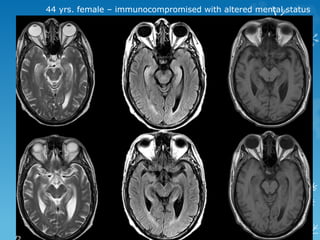

44 yrs. female – immunocompromised with altered mental status

44 yrs. female– immunocompromised with altered mental status